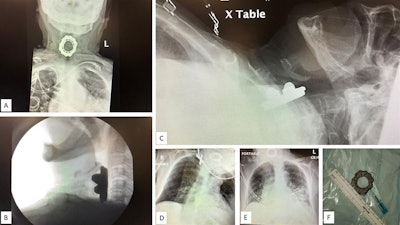

Three days after she was admitted to the hospital, a new medical team took over and noticed the woman had noisy breathing, which occurs with obstructed air flow. The team reexamined the previously obtained chest x-ray and brain and chest CT scans. The images revealed a large foreign body in the woman's hypopharynx-upper esophagus. The object was not described in the report initially read by junior radiology residents.

The patient failed a swallow study, and images were acquired of her neck soft tissue and anterior-posterior cervical spine, which revealed a 5.4 x 2.3 x 4.3-cm foreign body lodged in her hypopharynx anterior to the C3-C6 vertebrae, the authors wrote.

The woman was placed under general anesthesia to avoid erratic movements that could result in puncturing her esophagus. An otorhinolaryngologist surgeon used direct laryngoscopy and angled forceps for the extraction. Rapid sequence induction without application of cricoid pressure was used due to the position of the object, which was a spinning-top toy, they wrote.